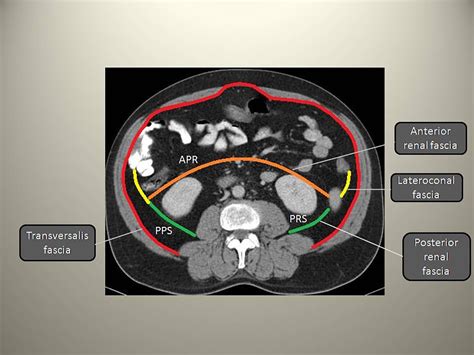

The perirenal fascia of Gerota is a dense layer of connective tissue that encloses the perirenal fat, the kidney, and the suprarenal (adrenal) gland. It is not merely a single sheet but rather a complex arrangement of anterior and posterior lamellae. Anatomically, these two layers fuse at different borders to create a contained space known as the perirenal space.

• Anterior Layer: Also known as the fascia of Toldt, this layer passes anterior to the kidney, renal vessels, and the great vessels (aorta and inferior vena cava).

• Posterior Layer: Also known as the fascia of Zuckerkandl, this layer attaches firmly to the fascia covering the psoas major and quadratus lumborum muscles.

• Lateral Fusion: The anterior and posterior layers fuse laterally to form the lateroconal fascia, which blends with the pararenal fascia.

• Medial Configuration: The arrangement is more complex medially, where the layers may remain separate or fuse around the great vessels, creating a barrier that restricts the movement of fluid across the midline.